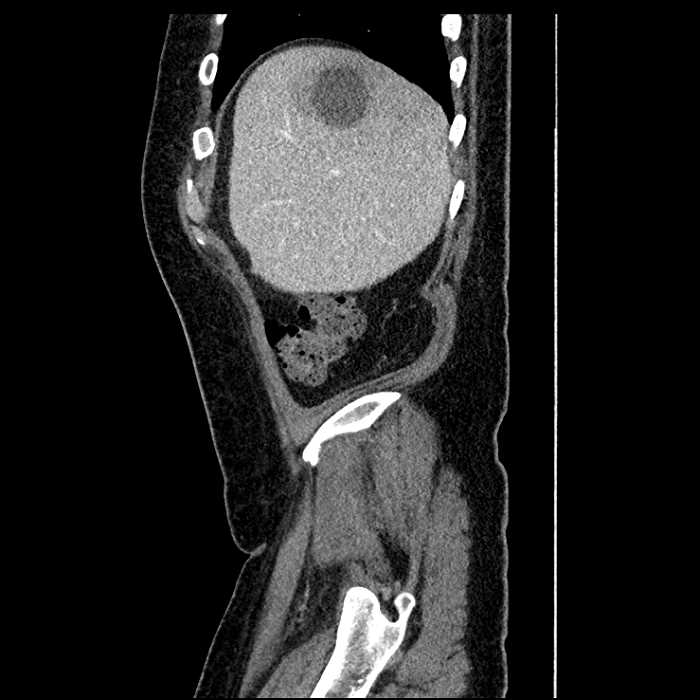

Age: 63

Sex: Male

Indication: Abdominal pain

• Large fluid density structure in hepatic segments 7 and 8 measuring 10 x 7 x 7 cm with internal septation and circumferential ill-defined low density compatible with edema

• Peripherally enhancing subcapsular collections along the anterior margin of the left hepatic lobe measuring 3 x 1 cm and 2 x 1 cm

• Clearly marginated fluid density structure in segment 7 and several other scattered tiny hypodensities, which likely represent cysts

• Hepatic abscess

Acute sigmoid diverticulitis complicated by a small contained perforation and a large abscess in the right hepatic lobe. Additional small subcapsular abscesses along the anterior margin of the left hepatic lobe.

• The classic CT imaging appearance is a double target sign with internal low density surrounded by an internal enhancing rim (capsule) and a low density external rim (edema)

Hepatic abscess showing the double target sign with low density internally surrounded by a thin inner enhancing rim (red arrow) and ill-defined outer low density rim (yellow arrow). Blue arrow indicates an internal septation. Red arrows: additional smaller subcapsular abscesses. Red arrow: focal contained perforation associated with diverticulitis.